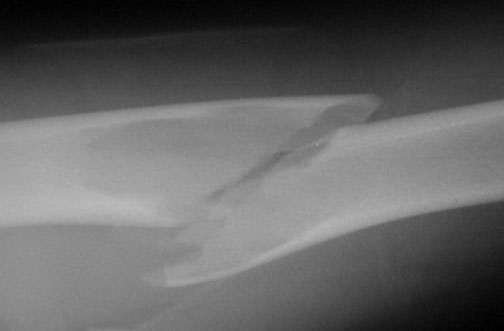

The pathologic fracture across a unicameral bone cyst in this radiograph of the humerus is evident. The area of lucency represents a unicameral bone cyst. The cyst weakened the bone so that a pathologic fracture occurred.